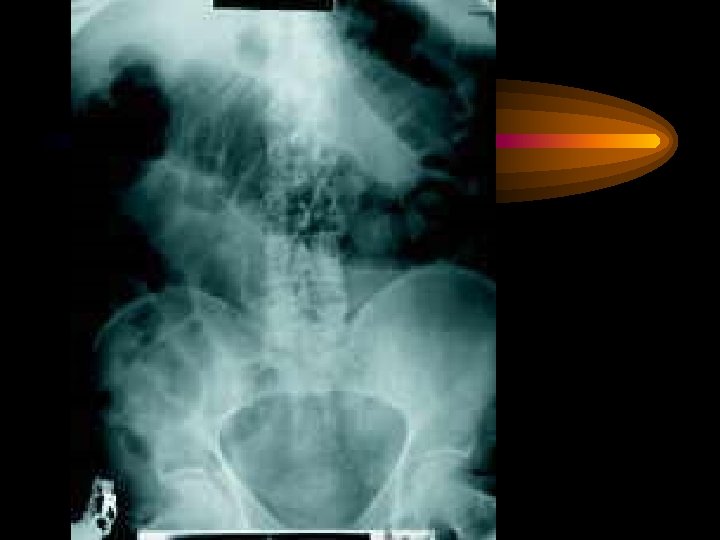

İnce barsak obstrüksiyonu